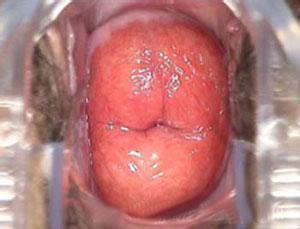

“分型护阴式平衡疗法”引延续中医精髓,将维持阴道酸碱平衡环境作为根治阴道炎的最终标准,针对病因,兼顾整体,分全身用药、局部用药。在治疗中,可根据病情采用中药制剂,用于阴道灌洗、上药,并配合光谱、水循环微波治疗进行立体式全方位的综合治疗。“分型护阴式平衡疗法,在利用美国真彩电子阴道镜准确、清晰观察阴道、宫颈等有关部位病变的前提下,先使用微波、光谱等高科技设备杀死深层组织内的微生物和炎症细胞,在有效控制炎症的同时,快速消除病灶。在物理治疗的基础上,再运用精选中药方剂离子雾化和深部灌洗,高效药物作用于患处等多种手段,促进阴道等部位的血液循环,改善机体营养供给,增强机体免疫力,从而达到消除炎症的目的,标本兼治,使得炎症不易复发。